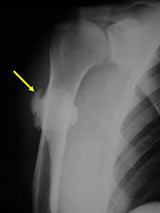

- Proximal humerus (15%); Tibia (10%); Fibula (3%), Radius, Ulna

- Lobulated and ossified exophytic mass (cauliflower-like) adjacent to the cortex; attached to metaphyseal cortex via a broad base

- Centrally, the tumor is radiodense (demonstrates ossification)

- Peripherally there may be small radiolucies that represent low grade cartilaginous lobules, fibrous tissue or fat

- The underlying cortex may be thickened

- There is no periosteal reaction since the tumor comes from the outer layer of the periosteum and therefore does not elevate the periosteum.